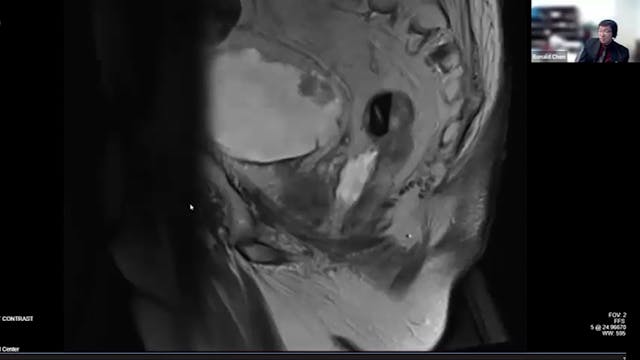

prostate cancer, local recurrence, PSA, ADT, fistula, cardiac comorbidity, brachytherapy, external beam radiation, high risk